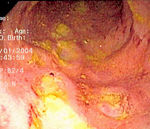

Endoscopy

A colonoscopy is the best test for making the diagnosis of Crohn's disease as it allows direct visualization of the colon and the terminal ileum, identifying the pattern of disease involvement. Occasionally, the colonoscope can travel past the terminal ileum but it varies from patient to patient. During the procedure, the gastroenterologist can also perform a biopsy, taking small samples of tissue for laboratory analysis which may help confirm a diagnosis. As 30% of Crohn's disease involves only the ileum, cannulation of the terminal ileum is required in making the diagnosis. Finding a patchy distribution of disease, with involvement of the colon or ileum but not the rectum, is suggestive of Crohn's disease, as are other endoscopic stigmata.The utility of capsule endoscopy for this, however, is still uncertain.